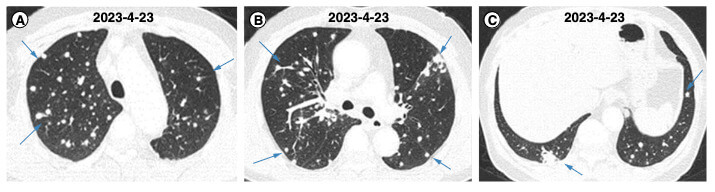

Computertomographieaufnahmen des Brustkorbs des Patienten bei der Erstuntersuchung. (A-C) CT-Bilder von verschiedenen Querschnitten. Credit: Y. Jiang et al

Die Computertomographie der Lunge bei der Aufnahme zeigt multiple noduläre Veränderungen in beiden Lungenflügeln. Auffällig sind zudem multiple vergrößerte Lymphknoten supraklavikulär links. Die Ärzte führen transthorakale Biopsien der nodulären Veränderungen in der Lunge durch. Die histopathologische Untersuchung zeigt normales Lungenparenchym mit Kohleablagerungen. Auch die supraklavikulären Lymphknoten werden biopsiert, wobei nur normale Lymphozyten in der Zytologie nachgewiesen werden.